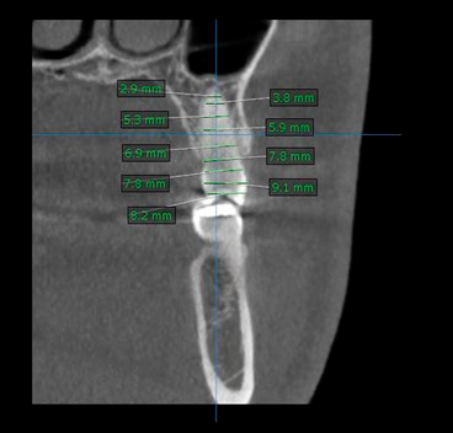

Se llevó a cabo un estudio transversal comparativo mediante tomografía computarizada del segundo premolar superior (Figura 1). Se diseñaron tres modelos, mediante software 3D, de un diente sin patologías, se excluyeron del estudio dientes premolares con restauraciones, caries y alteraciones de morfología. El implante personalizado de titanio grado 5, con forma exacta del segundo premolar, se comparó con el implante de titanio Zimmer® TSV de 4.1mm x 13 mm. Con tomografía computarizada del segundo premolar superior, los archivos formato DICOM de TC se ingresaron al software de reconstrucción tridimensional Mimics® (Materialise, Lovaina, Bélgica) obteniendo un modelo sólido. El modelo CAD de bloque óseo maxilar posterior simplificado con hueso cortical palatal y vestibular correspondiente se obtuvo utilizando el software SolidWorks® CAD (SolidWorks Corp., Concord, Massachusetts, Estados Unidos). El bloque óseo edéntulo con alveolo dental de extracción simulado por eliminación de primer molar superior del modelo de elemento finito (EF*) se compuso de hueso cortical, hueso esponjoso, implantes, tornillos de titanio, pilares, prótesis de implantes posterior, corona total cerámica, diente natural y ligamento periodontal. Para la simulación de las cargas naturales desde la contraparte mandibular a la superficie oclusal al eje largo del implante personalizado, implante convencional (Zimmer TSV de 4.1 mm x 13 mm) y diente (Figura 2 A-C)7; se realizó en un ángulo perpendicular al eje del diente; además, se aplicó una carga de 7.5 N, 100 N y 150 N a la superestructura del modelo realizado para cada caso. Los materiales de los modelos se consideraron isotrópicos, homogéneos y linealmente elásticos8. Las propiedades mecánicas utilizadas para la simulación EF* son sustentadas en la Tabla 1.